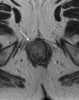

Anal carcinoma

Anal cancer is a cancer which arises from the anus, the distal opening of the gastrointestinal tract. Symptoms may include bleeding from the anus or a lump near the anus. [Source: Wikipedia ]